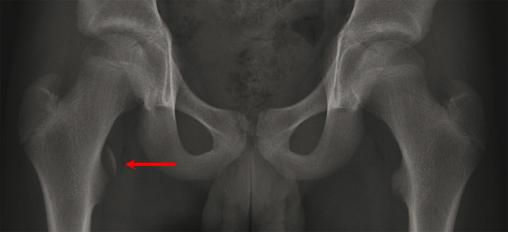

© P. Journeau, E. Polirzstok, F. Launay, D. Barbier (La Revue du Praticien)

Avulsion de l'insertion du muscle psoas. Voir : P. Journeau, E. Polirzstok, F. Launay, D. Barbier. Lésions osseuses de sollicitation excessive chez l’enfant sportif. Rev Prat 2015;65(8);1084-90.